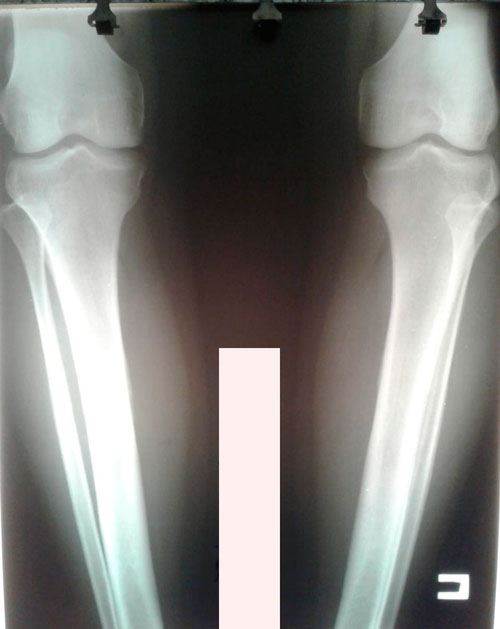

Ноги в сравнении, с чем приехали в Клинику